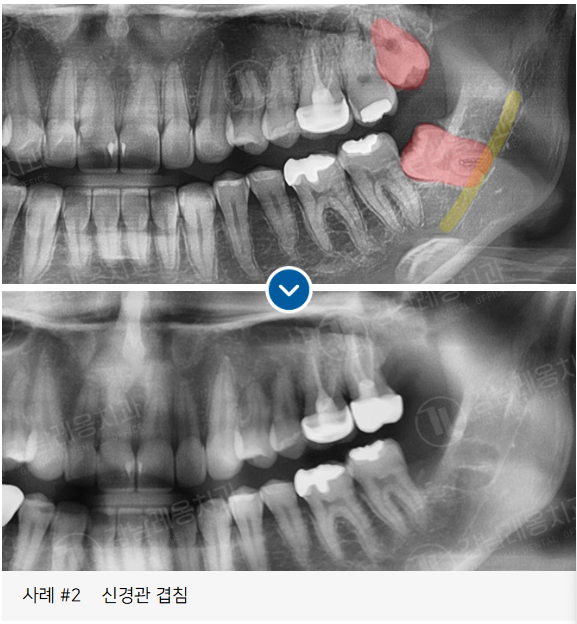

✅ 아래턱 신경과 매우 가까운 위치의 사랑니

고난도 케이스 경험 다수

사랑니 발치로 강남레옹치과에 방문해주시는

40~50%가 수평/매복 사랑니이며

아래와 같은 고난도 케이스도

충분한 상담을 통해

사랑니 진료를 진행하고 있습니다.